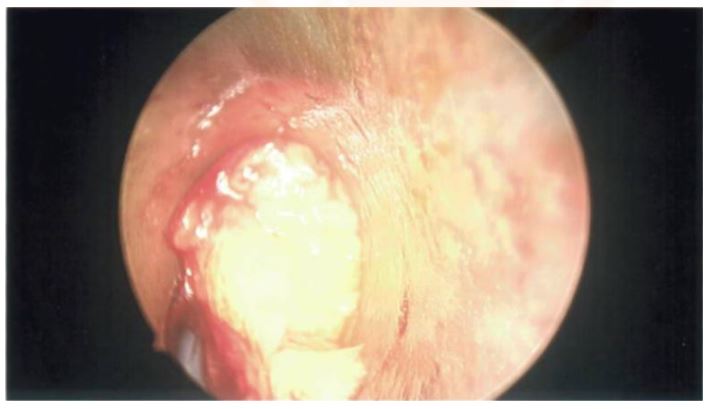

In November 2023, the patient underwent orotracheal intubation and endoscopic excision of the mass via microlaryngoscopy under general anaesthesia with a stepwise approach (see Figures 2A, 2C & 2D).The true and false vocal cords were fully visualised and seen to be healthy (see Figure 2B).The fatty mass was nearly completely resected using a cold steel technique assisted by endoscopy. Minimal bleeding was observed during the operation and no postoperative complications occurred.

The patient exhibited a successful recovery following the operation. During the one-month follow-up, transnasal flexible endoscopy revealed the absence of any residual disease. The mucosa overlying the excision site was intact and both vocal cords were observed to be bilaterally healthy and mobile. This patient will continue to undergo periodic surveillance over a two-year period as per previous histopathology recommendation.